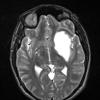

NEOPLASMS (GLIAL)

Astrocytoma, IDH-mutant, WHO Grade 2 (5)